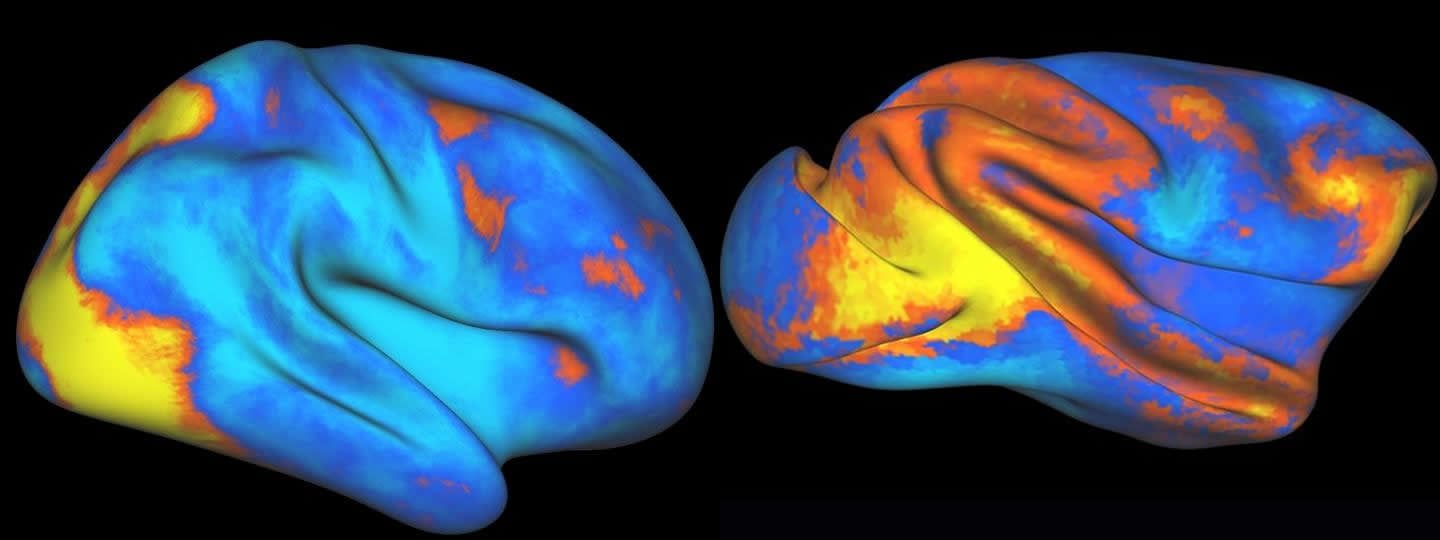

In a series of experiments, first using a primate model at Washington University in St. Louis, and later with human subjects at CUMC, the researchers used functional magnetic resonance imaging (fMRI) to map brain activity. Before the start of a session, the subject memorized a specific target object. During the session, a stream of images appeared on various parts of a screen. The subject pushed a button when the target object appeared on the screen. fMRI technology allowed the researchers to see when various parts of the brain ‘switched on’ while the subject performed the task. And the results were surprising.

“The fMRI showed striking differences between the two species, which was wholly unexpected,” said Dr. Patel. “We were giving both the human and primate subjects the exact same task—their brain activity should have been more similar. That’s when we realized there was something else going on.”

First, they realized that the VAN—located in the right hemisphere of the human brain—had no equivalent in the primate brain. They also noticed the DAN had expanded in the human subjects, and observed enhanced cross talk between the human subjects’ brain hemispheres.

Image Credit: The images are credited to Gaurav Patel/New York State Psychiatric Institute/Columbia University Medical Center